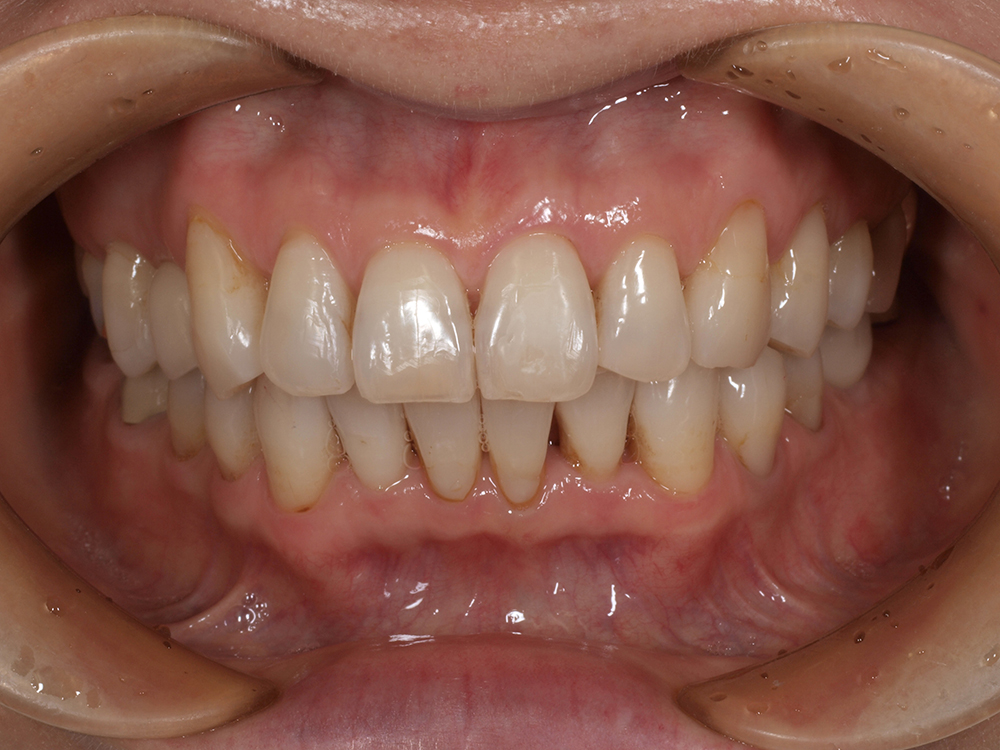

53歳 男性

- 主訴

- 全然噛めない。上の歯が取れてきた

- 処置内容

- 上顎:8本 下顎:2本

- 治療費用

- 上顎:約320万円(税込)、下顎:約160万円(税込)

- 治療期間

-

上顎:1年(仮歯まで8か月)

下顎:8か月(仮歯まで5か月)

- リスク

- 上部構造物、仮歯の破折、術後の腫れ(3日)、人工歯根脱落リスクがあります